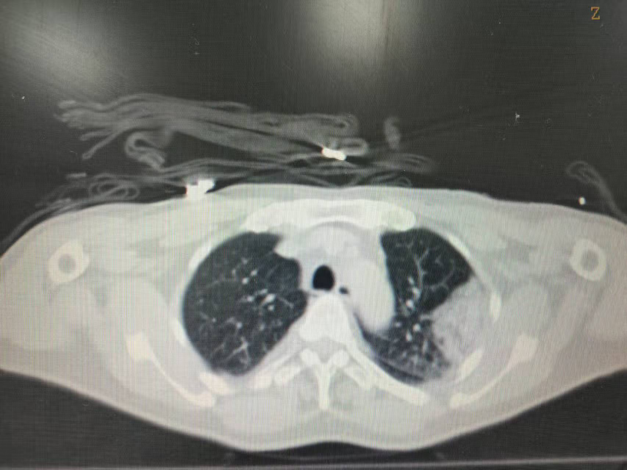

术后即刻CT平扫,冷冻范围超过病灶边界5mm